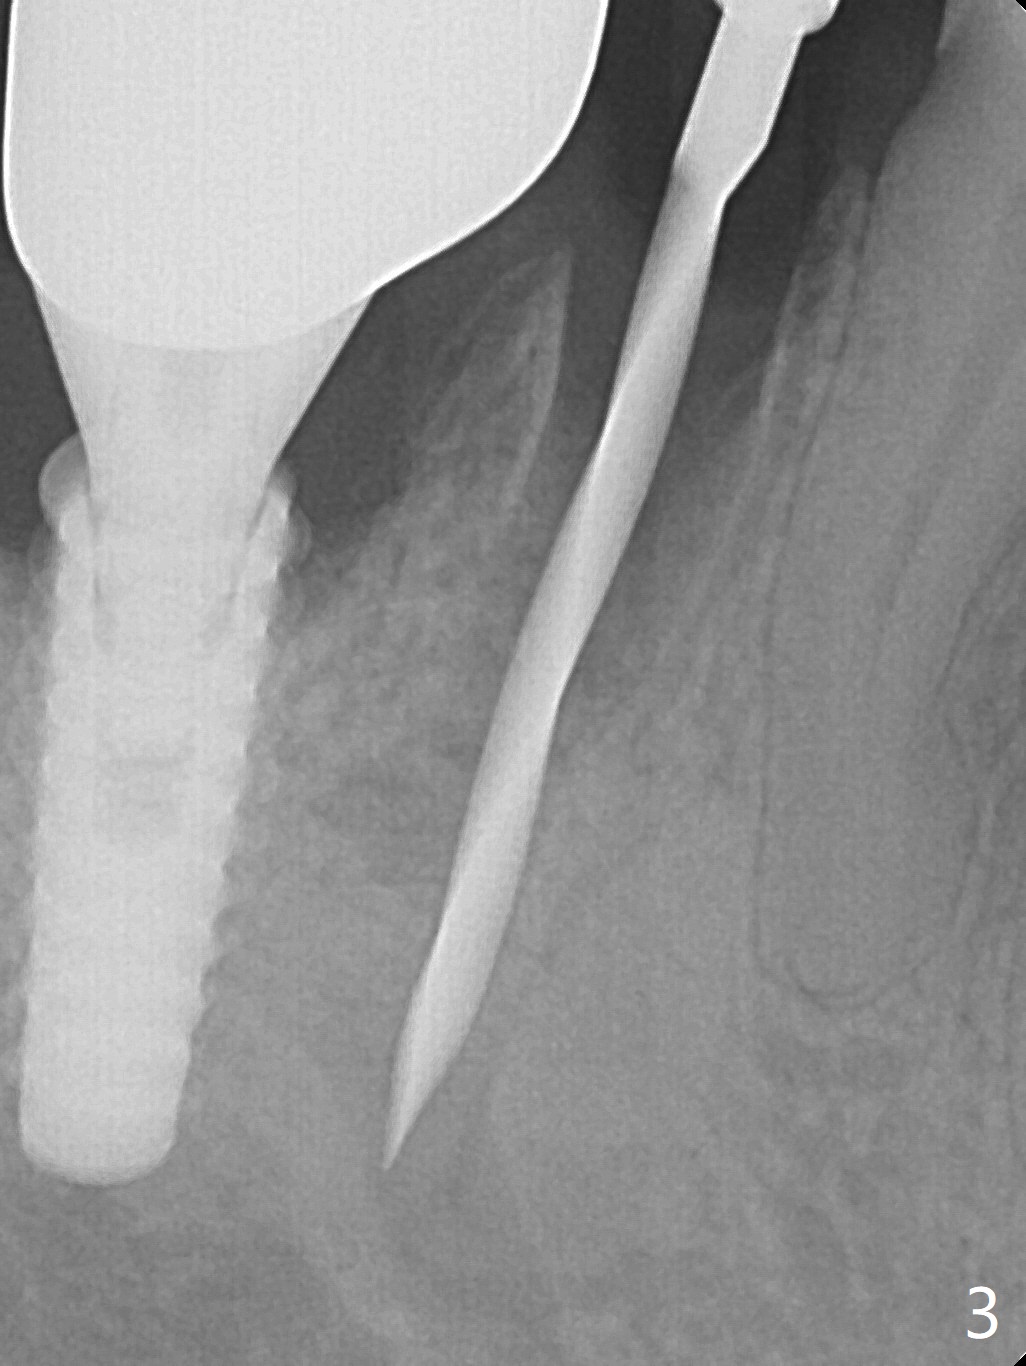

The tooth #29 has mild persistent pain radiating to the temple with mild percussion and mobility I 4.5 months post apicoectomy; the buccal recession is noticeable (Fig.1). Granulation tissue and bone graft are attached to the resected apex of the extracted tooth (Fig.2 <). The initial osteotomy with 1.5 mm drill is distal (Fig.3). After position adjustment with difficulty because of hard bone, osteotomy is finished with 2.8 and 3.2 mm Magic Drills (Fig.4). Following final drill, a 3.5x11 mm IBS implant is placed with insertion torque of 45 Ncm. With placement of a 4.5x4(4) mm abutment, Vanilla graft is placed in the buccal gap (Fig.5). Immediately postop CT shows that the implant is buccally placed (Fig.6,7 B). In fact after extraction (Fig.8), the initial osteotomy should start obliquely and as coronal and lingual as possible (Fig.9 red line). Following the initial penetration, the osteotomy should be straightened (Fig.10) so that the implant could be placed lingually (Fig11 green) to reduce buccal thread exposure. In fact there is also buccal thread exposure at #30 (Fig.12). The bone loss at #29 and 30 is minimal 4 months postop (#29, Fig.13 *)) and severe with periimplantitis at #29 one year post cementation (Fig.14). Incision will be made to exposure buccal threads of #29 and 30. If threads are within bone boundary, bone graft will be done with sticky bone after Titanium brush. If not, remove implant threads and bone graft. The worst scenario will be handled with implant removal (trephine bur 4/5 mm), either with bone graft or implant being placed lingually (IBS 3x11 mm 2-piece, to be buried, if needed (Fig.15)). Take preop photos to show #29 and 30 buccal recession and gingival erythema.